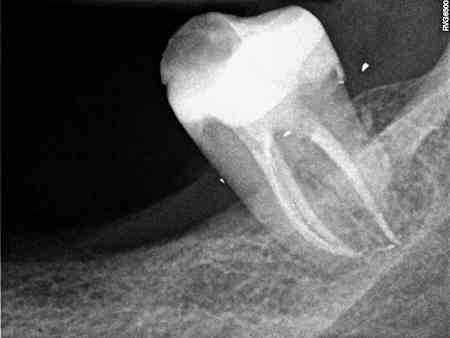

De endodontie of wortelkanaalbehandeling bestaat uit het verwijderen van zenuwen die zich in de wortels van de tanden bevinden. Na het verwijderen zal de tand weer opgevuld worden. Deze behandeling zal u weer een comfortabel gevoel geven.